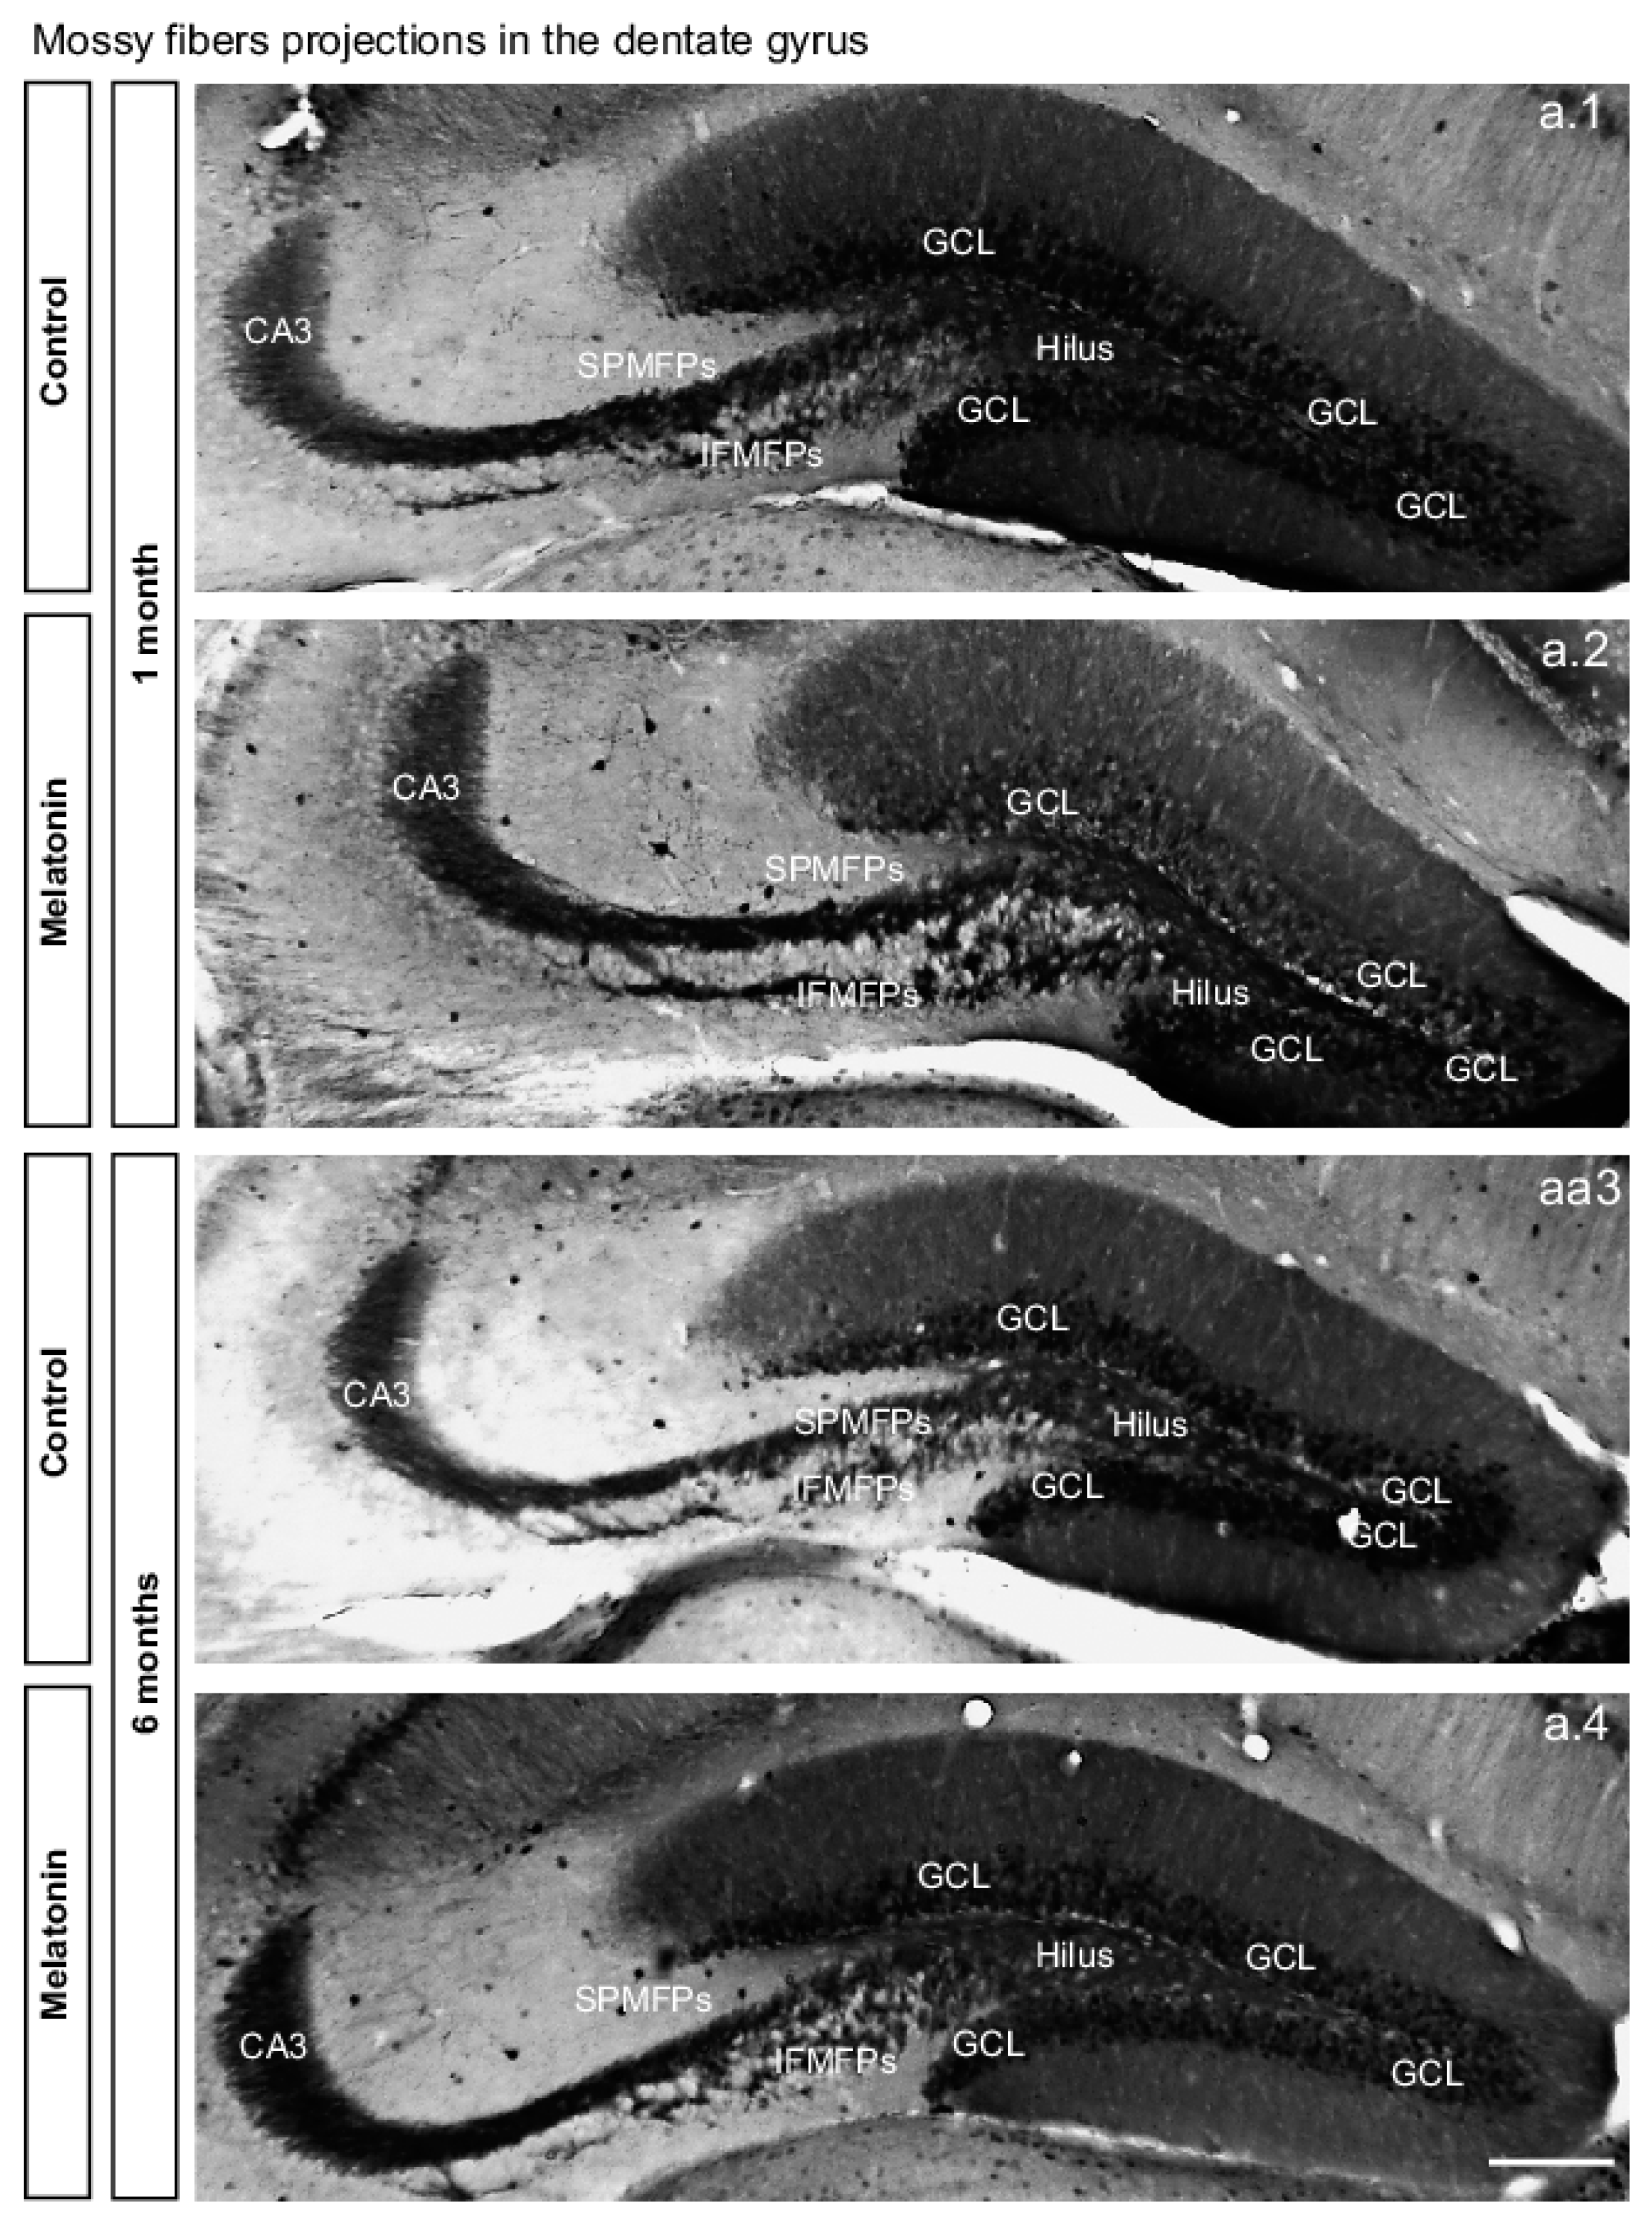

2.2. Melatonin Modulates Plasticity of Axons in Granule Cells in the Dentate Gyrus in Male Balb/c Mice